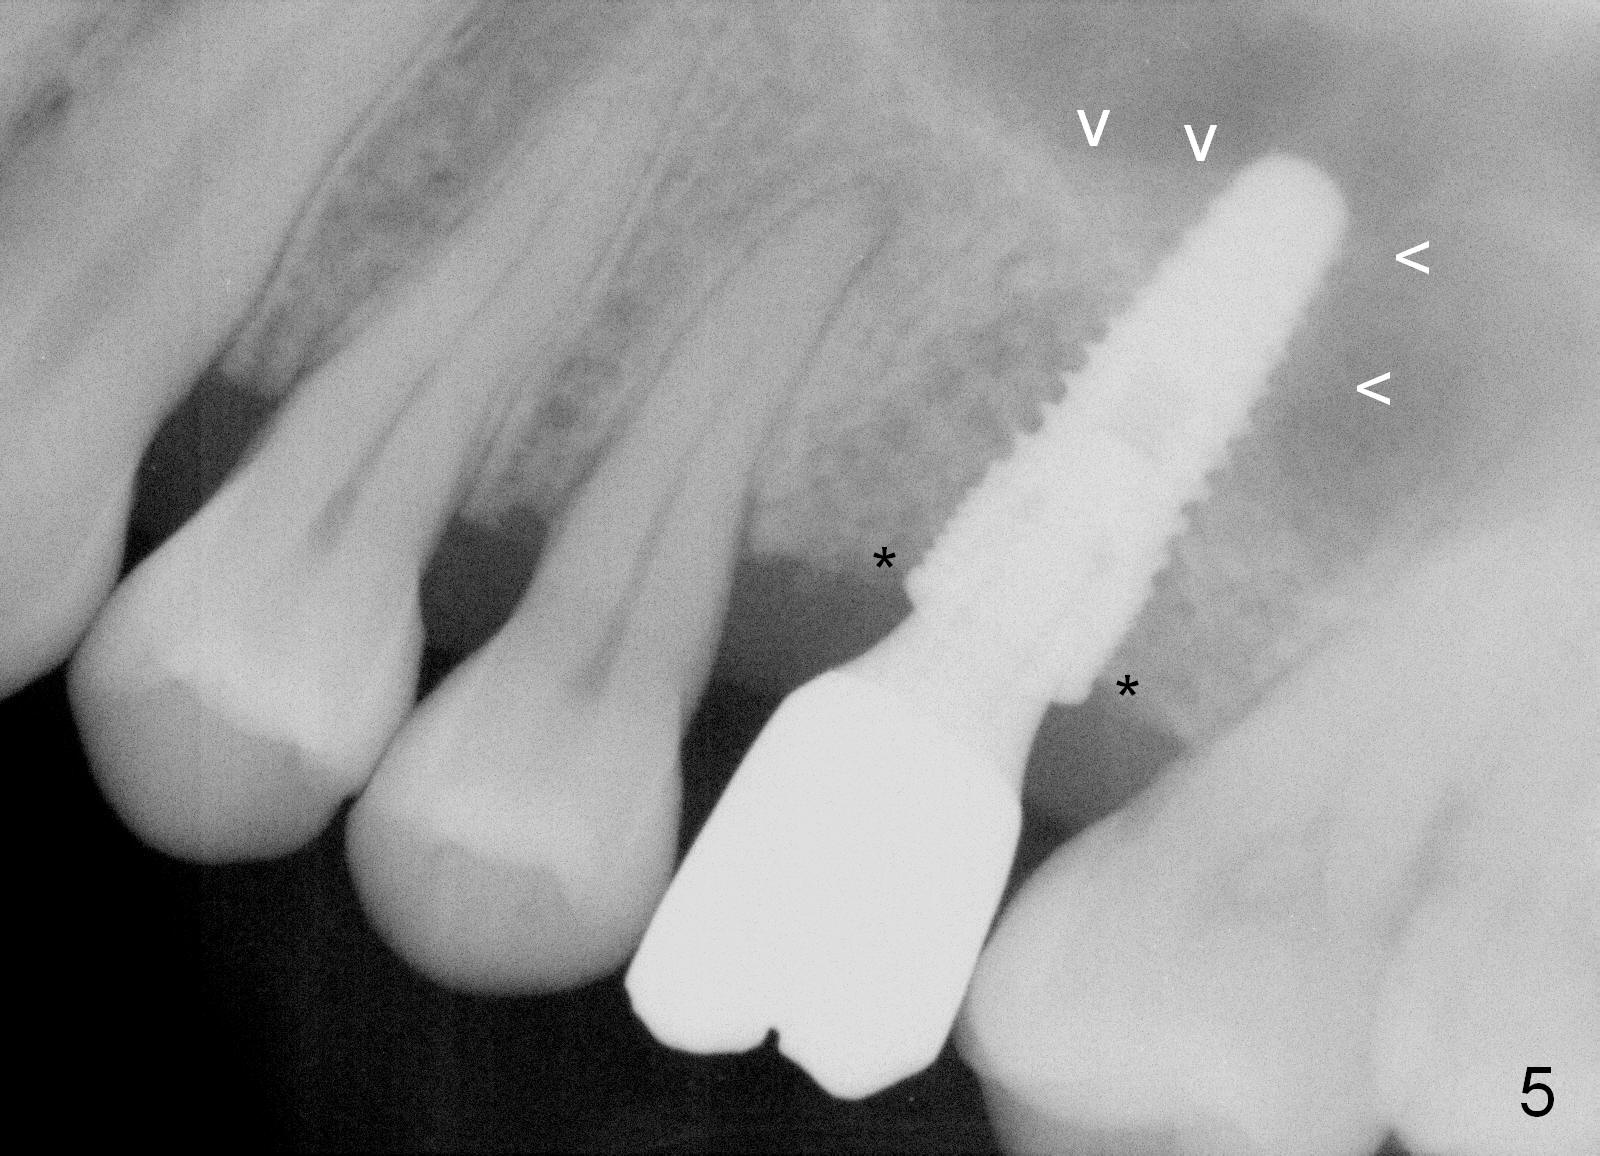

The patient returns for follow up 2.5 months post cementation. There is no crestal bone resorption (Fig.5 *), while the bone still surrounds the apex of the implant (arrowheads).